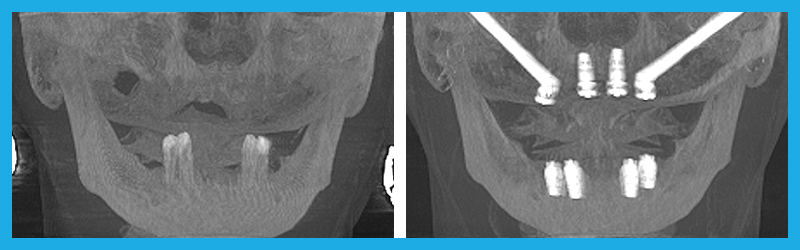

- Zygomatic and Pterygoid Implants: A Faster Solution: Traditional dental implant methods often require extensive bone grafting and a lengthy healing period, sometimes taking up to a year before final teeth are placed. Zygomatic and Pterygoid Implants bypass the need for bone grafts by anchoring the implants in the cheekbone and pterygoid plate, allowing for immediate loading of teeth. This not only shortens the treatment time dramatically but also provides a solution for patients who were previously told they weren’t candidates for implants due to severe bone loss.

Before and After

Zygomatic Implants